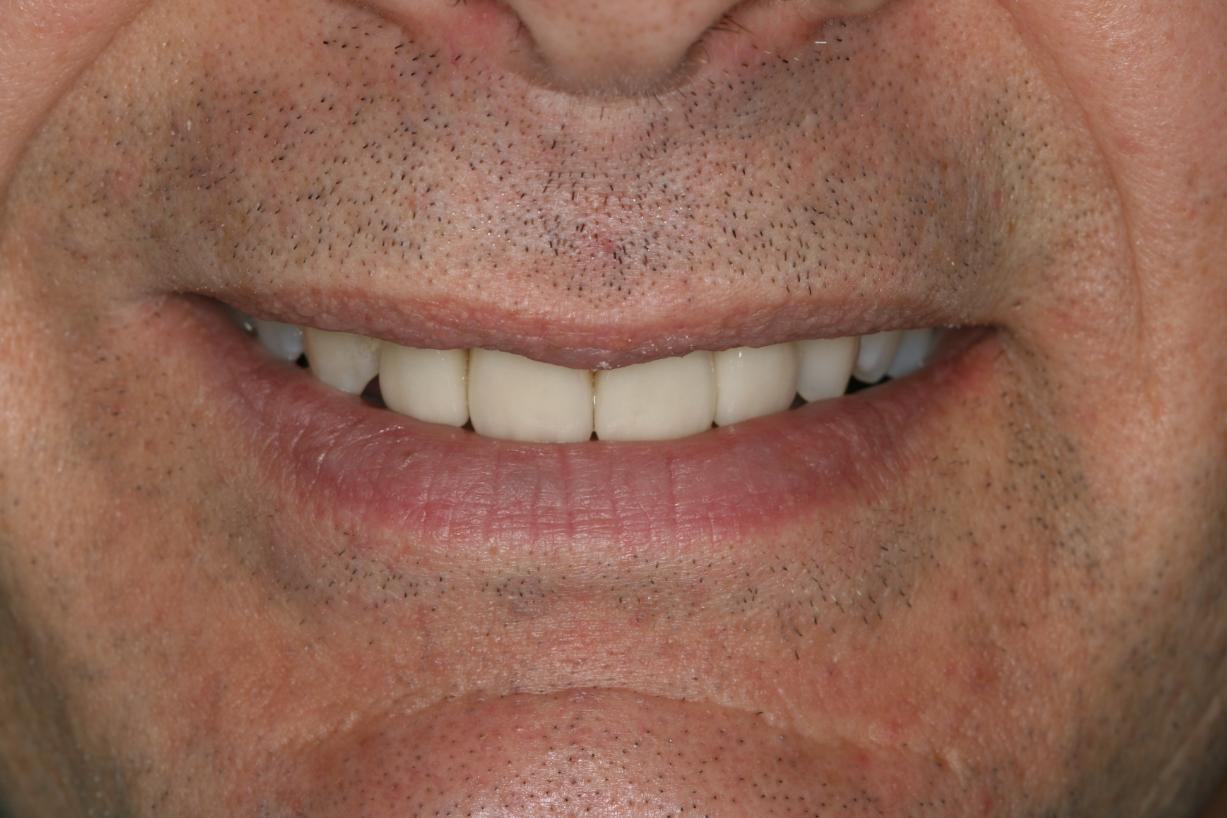

Before & After